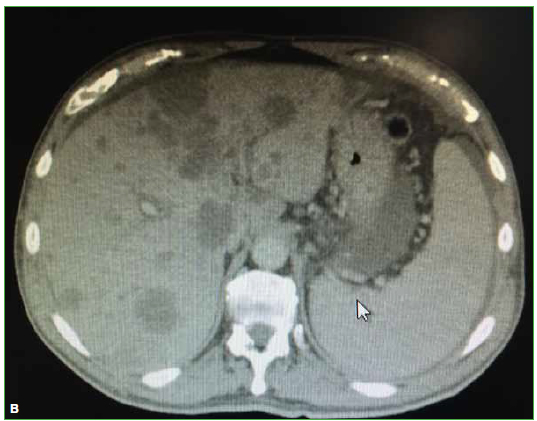

Las hernias discales intraesponjosas vertebrales o nódulos de Schmörl consisten en una herniación o una extrusión del núcleo pulposo del disco intervertebral a través del platillo vertebral hacia el cuerpo adyacente. Suelen asociarse a deformidades vertebrales, como la enfermedad de Scheuermann, o a enfermedades reumáticas, como la espondilitis anquilopoyética. En general, son hallazgos casuales y cuadros asintomáticos; son pocos los casos publicados de nódulos sintomáticos. Su aparición estaría relacionada con un platillo vertebral debilitado por traumatismo o estrés repetido. Cuando el nódulo es agudo o reciente, puede ser difícil diferenciar la degeneración benigna de una infiltración maligna o una infección. Presentamos un caso inusual de un nódulo de Schmörl doloroso en un hombre sin antecedentes de relevancia, que enmascaró una lesión metastásica de carcinoma pancreático a nivel lumbar. Se realiza una revisión bibliográfica. ABSTRACTIntraosseous disc herniation –or Schmörl nodes (SN)– are a herniation or prolapse of the nucleus pulposus of the intervertebral disc through the vertebral plate and into the adjacent vertebral body. They are usually associated with vertebral deformities, suchas Scheuermann’s disease, or rheumatic diseases, such as ankylopoietic spondylitis. In general, they are spontaneous and asymptomatic findings, and there are only a few reported cases of symptomatic nodes. The etiology is supposedly related to a weakened spinal plate due to trauma or repeated stress. When the node is acute or recent, it can be difficult to differentiate a benign degeneration from a malignant infiltration or infection. In this paper, we discuss the unusual case of a painful Schmörl node in a man with no relevant history and a masked metastatic lumbar spinal tumor originated from pancreatic cancer. We performed a literature review.Descargas